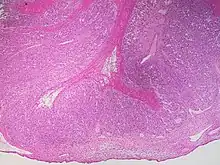

This type of functional cyst occurs after an egg has been released from a follicle. The follicle then becomes a secretory gland that is known as the corpus luteum. The ruptured follicle begins producing large quantities of estrogen and progesterone in preparation for conception. If a pregnancy doesn't occur, the corpus luteum usually breaks down and disappears. It may, however, fill with fluid or blood, causing the corpus luteum to expand into a cyst, and stay in the ovary. Usually, this cyst is on only one side, and does not produce any symptoms.[1][2]

A ruptured corpus luteum can cause hemoperitoneum with abdominal pain, and is a common condition in women of reproductive age. It may be confused with ectopic pregnancy.[4]